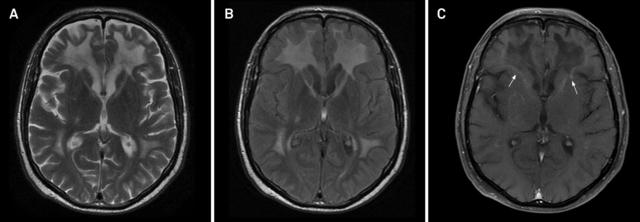

案例 4:28 岁患者,诊断为异染性脑白质营养不良。

图 4 可见额叶为主的白质高信号伴轻度脑萎缩

案例 5:1 例晚发 病患者。

图 5 A~B:T2WI 可见双侧半卵圆中心至内囊后肢的皮质脊髓束对称性高信号,胼胝体压部亦有受累

案例 6:44 岁女性,诊断为 病。

图 6 FLAIR / T2WI 提示脑白质病变,累及锥体束